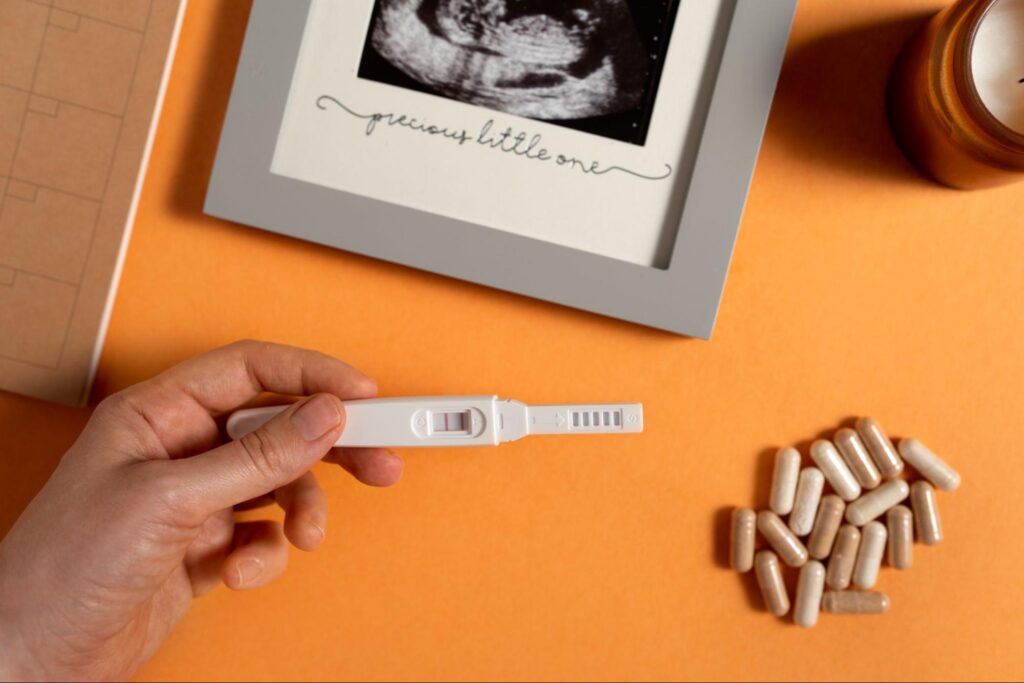

يقوم الطبيب بوصف بعض الأدوية الهامة بعد نجاح محاولة الحقن المجهري وإثبات وجود الحمل، حيث تساعد تلك الأدوية على دعم صحة الأم و الجنين، إذ تتضمن تلك الأدوية على بعض الفيتامينات ومنها حمض الفوليك الذي لديه دورًا هامًا في نمو الجنين، ووقايته من تشوهات الأنبوب العصبي الذي يتطور لاحقًا إلى الدماغ والحبل الشوكي، بالإضافة إلى مهمته في تكوين خلايا الدم الحمراء التي تساعد على نقل الدم إلى جميع أعضاء الجسم للجنين.

يصف الطبيب أيضًا بعض الأدوية الهرمونية مثل هرمون البروجسترون، وذلك لتثبيت الجنين في بطانة الرحم، ودعم الحمل في مراحله الأولى، بالإضافة إلى وصف بعض الأدوية المضادة للغثيان والحموضة، وذلك للتخفيف من الشعور بهما خلال الأشهر الأولى من الحمل.

وفي الختام، إن رحلة الحمل بعد الحقن المجهري قد تكون صعبة، لكنّها ليست مستحيلة، و باتباع تعليمات الطبيب المعالج ستتمكن المرأة الحامل من زيادة فرصتها في ولادة طفلٍ سليم.